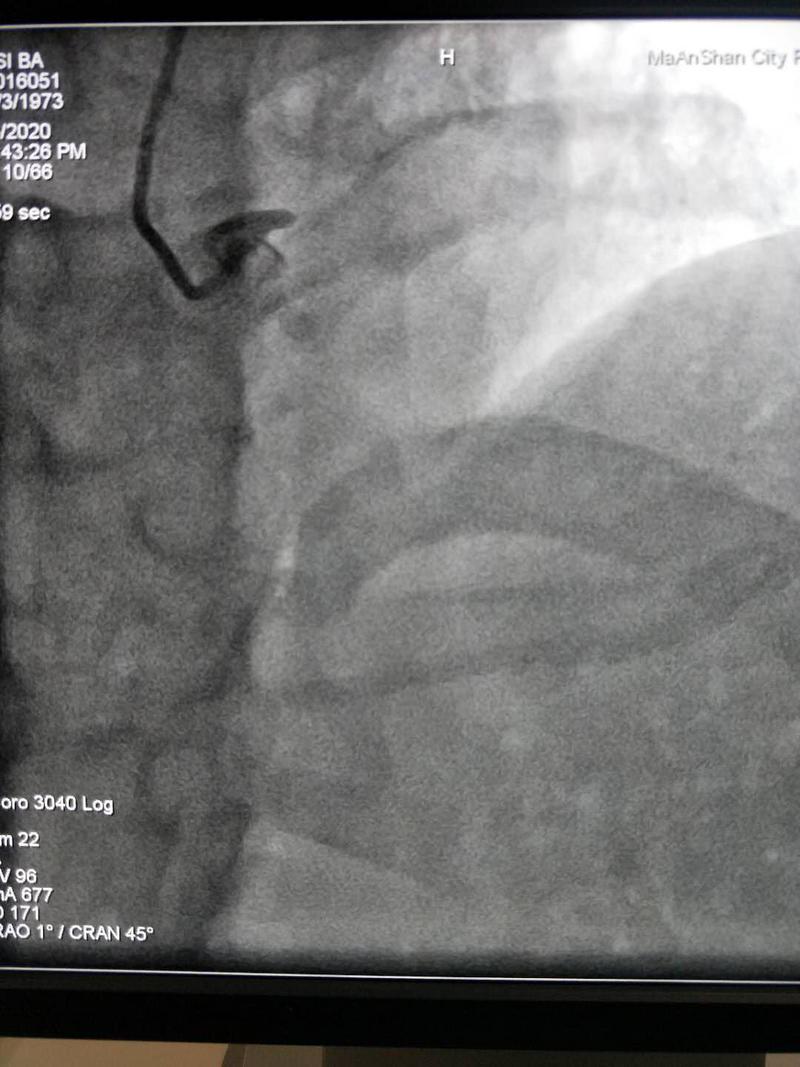

此患者因“活動后胸痛3年,加重1周入院”,門診雙源CT冠脈CTA提示:RCA、LM、LAD、LCX多發(fā)斑塊形成,管腔多發(fā)狹窄,其中最明顯處位于左主干。入院后患者心絞痛發(fā)作頻繁,經(jīng)驗(yàn)豐富的心內(nèi)科邵旭武副主任分析患者左主干閉塞可能性極大,隨時可能出現(xiàn)猝死。立即與家屬溝通行冠脈造影術(shù),左側(cè)冠狀動脈造影提示左主干自體部完全閉塞,隨后分出的前降支、回旋支都沒有血供;右側(cè)冠狀動脈造影可見右冠遠(yuǎn)端向前降支、回旋支發(fā)出側(cè)支循環(huán),細(xì)細(xì)的側(cè)支循環(huán)維系著患者左心室的心肌細(xì)胞血供,真正的命懸一線,左主干CTO?。?!

開通前